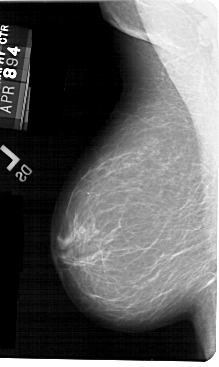

A_1548_1.LEFT_CC

LEFT_CC LINES 5356 PIXELS_PER_LINE 3136 BITS_PER_PIXEL 12 RESOLUTION 43.5 NON_OVERLAY